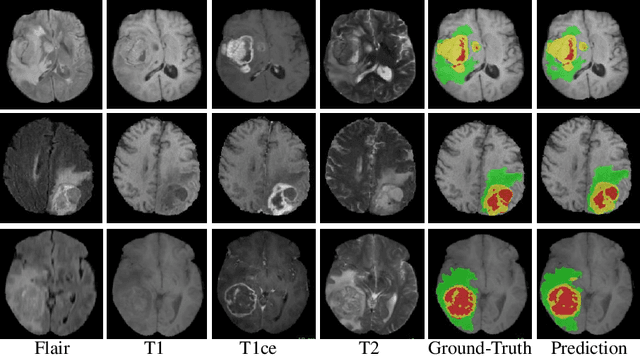

Abstract:In this work, we develop an attention convolutional neural network (CNN) to segment brain tumors from Magnetic Resonance Images (MRI). Further, we predict the survival rate using various machine learning methods. We adopt a 3D UNet architecture and integrate channel and spatial attention with the decoder network to perform segmentation. For survival prediction, we extract some novel radiomic features based on geometry, location, the shape of the segmented tumor and combine them with clinical information to estimate the survival duration for each patient. We also perform extensive experiments to show the effect of each feature for overall survival (OS) prediction. The experimental results infer that radiomic features such as histogram, location, and shape of the necrosis region and clinical features like age are the most critical parameters to estimate the OS.

Abstract:Segmentation of brain tumor from magnetic resonance imaging (MRI) is a vital process to improve diagnosis, treatment planning and to study the difference between subjects with tumor and healthy subjects. In this paper, we exploit a convolutional neural network (CNN) with hypercolumn technique to segment tumor from healthy brain tissue. Hypercolumn is the concatenation of a set of vectors which form by extracting convolutional features from multiple layers. Proposed model integrates batch normalization (BN) approach with hypercolumn. BN layers help to alleviate the internal covariate shift during stochastic gradient descent (SGD) training by zero-mean and unit variance of each mini-batch. Survival Prediction is done by first extracting features(Geometric, Fractal, and Histogram) from the segmented brain tumor data. Then, the number of days of overall survival is predicted by implementing regression on the extracted features using an artificial neural network (ANN). Our model achieves a mean dice score of 89.78%, 82.53% and 76.54% for the whole tumor, tumor core and enhancing tumor respectively in segmentation task and 67.90% in overall survival prediction task with the validation set of BraTS 2018 challenge. It obtains a mean dice accuracy of 87.315%, 77.04% and 70.22% for the whole tumor, tumor core and enhancing tumor respectively in the segmentation task and a 46.80% in overall survival prediction task in the BraTS 2018 test data set.